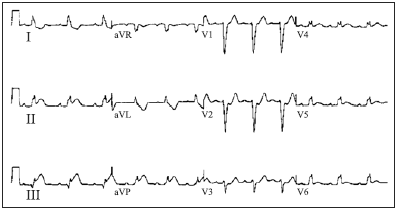

Homem, 75 anos, com antecedentes de hipertensão arterial sistêmica, ex-tabagista, diabético e dislipidêmico, em uso de atenolol, AAS, metformina, glibenclamida e sinvastatina, chega ao pronto-atendimento com queixa de dor retroesternal há, pelo menos, 2 horas, acompanhada de sudorese intensa, dispneia e náuseas. O exame físico da admissão revela o paciente em regular estado geral, taquipneico leve, palidez cutaneomucosa e sudoreico. PA = 160 x 90 mmHg, FC = 50 bpm, SO2 = 96% em ar ambiente. O exame físico revela auscultas cardíaca e pulmonar normais. O eletrocardiograma realizado no momento da admissão encontra-se ilustrado a seguir.

(Considere: PR = 220 ms; FC = 50 bpm; duração do QRS = 130 ms)

Homem, 75 anos, com antecedentes de hipertensão arterial sistêmica, ex-tabagista, diabético e dislipidêmico, em uso de atenolol, AAS, metformina, glibenclamida e sinvastatina, chega ao pronto-atendimento com queixa de dor retroesternal há, pelo menos, 2 horas, acompanhada de sudorese intensa, dispneia e náuseas. O exame físico da admissão revela o paciente em regular estado geral, taquipneico leve, palidez cutaneomucosa e sudoreico. PA = 160 x 90 mmHg, FC = 50 bpm, SO2 = 96% em ar ambiente. O exame físico revela auscultas cardíaca e pulmonar normais. O eletrocardiograma realizado no momento da admissão encontra-se ilustrado a seguir.

(Considere: PR = 220 ms; FC = 50 bpm; duração do QRS = 130 ms)

Leia o enunciado a seguir e responda às questões de números 51 a 53.

Homem, 75 anos, com antecedentes de hipertensão arterial sistêmica, ex-tabagista, diabético e dislipidêmico, em uso de atenolol, AAS, metformina, glibenclamida e sinvastatina, chega ao pronto-atendimento com queixa de dor retroesternal há, pelo menos, 2 horas, acompanhada de sudorese intensa, dispneia e náuseas. O exame físico da admissão revela o paciente em regular estado geral, taquipneico leve, palidez cutaneomucosa e sudoreico. PA = 160 x 90 mmHg, FC = 50 bpm, SO2 = 96% em ar ambiente. O exame físico revela auscultas cardíaca e pulmonar normais. O eletrocardiograma realizado no momento da admissão encontra-se ilustrado a seguir.

(Considere: PR = 220 ms; FC = 50 bpm; duração do QRS = 130 ms)

Em relação aos achados eletrocardiográficos, é correto afirmar que